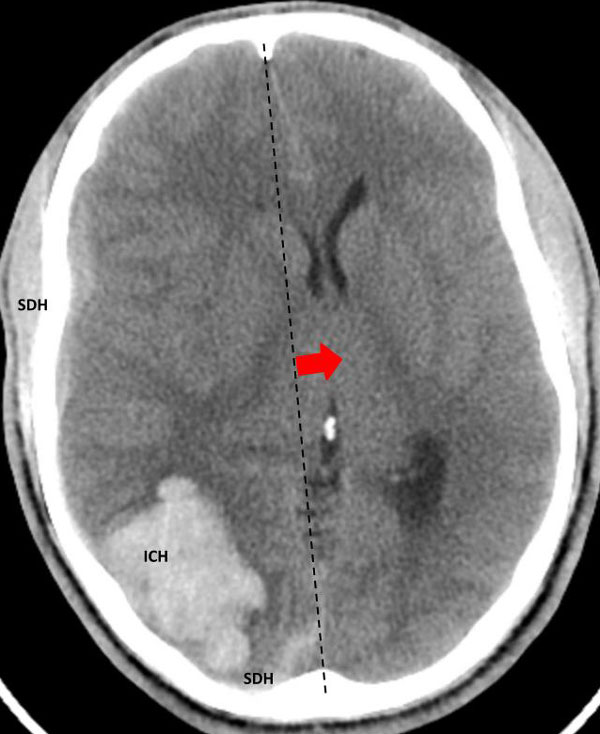

The student underwent NBCA-embolization of the AVM via the dominant feeding posterior cerebral artery with care to avoid embolizing the calcarine branches and avoid NBCA penetration into the single draining vein (Fig 4 and 5). Following the intervention, a tiny feeder from the middle cerebral artery remained (Fig 4).

Fig 5. Comparison, pre (5A) and post-embolization (5B) AP view, late-arterial phase of a right internal carotid artery (ICA) injection. On the right, near total obliteration of the AVM (red arrow). Draining vein (yellow star), residual veins (blue stars).